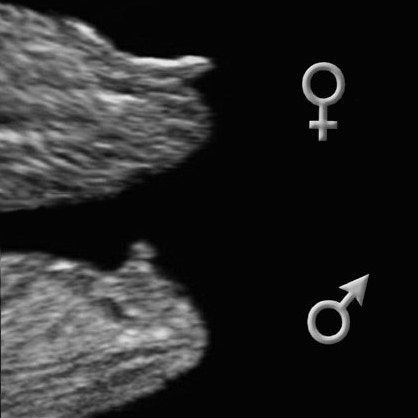

А, да, посмотрите фотки - 100% же девочка 🤣 нафига я делала анализ крови и так все видно😂 прямо откровенно не мальчик

Ольга Жаркова, в 12 недель и у девочки будет этот «писюн», только это не писюн, а половой бугорок, из которого потом будут формироваться половые органы. В зависимости от наклона бугорка можно предположить пол.